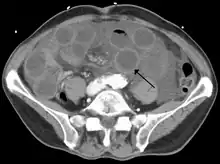

Computed tomography (CT) showing dilated loops of small bowel with thickened walls (black arrow), findings characteristic of ischemic bowel due to thrombosis of the superior mesenteric vein.

Risk factors for acute intestinal ischemia include atrial fibrillation, heart failure, chronic kidney failure, being prone to forming blood clots, and previous myocardial infarction.[2] There are four mechanisms by which poor blood flow occurs: a blood clot from elsewhere getting lodged in an artery, a new blood clot forming in an artery, a blood clot forming in the superior mesenteric vein, and insufficient blood flow due to low blood pressure or spasms of arteries.[3][6] Chronic disease is a risk factor for acute disease.[7] The best method of diagnosis is angiography, with computed tomography (CT) used when that is not available.[1]